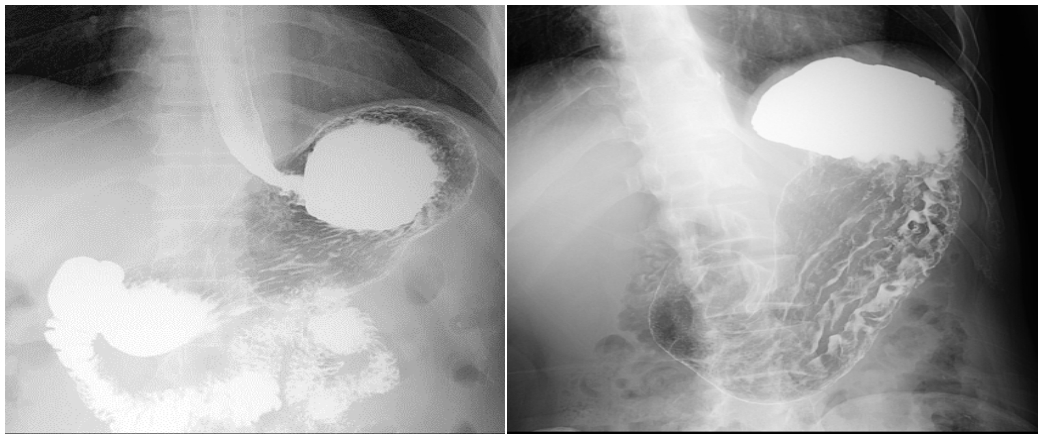

上消化道造影经常用于诊断上消化道的炎症性疾病、溃疡类疾病、胃石、胃扭转、肿瘤类疾病、胃食管术后评估等等。该检查简单易行,除了能显示上消化道的解剖结构外,也可以显示消化道管腔的舒张和收缩功能。但简单易行的事想要做好就离不开被检查者的有效配合。下面我们一起来看看做上消化道造影检查前,您需要了解的事儿吧。